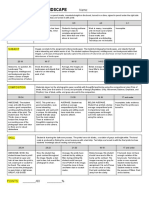

Notebook9

SammyPuccini

Artifact Causes Appearance

Dirtonoptics(lenses, Notcleaned Horizontalwhitelines

mirror,andlightguide

DamagedIRplate Wear/tear,handling Cracksposingasforeignbodies,radiolucentandwhite

Ghosting Incompleteerasure Canseeotheranatomy,besidestheanatomytheimagebeingtaken.Ex:pelvisonachest

Platereader Platereader Lines/patternsontheimage

electronic

malfunctioning,

appearsonmultiple

imagesnotonsame

plate

Backscatterartifacts Backscatter Darklinesontheimage,blackandradiopaque

transmittedthrough

cracksintheplate

Quantummottle Notenoughradiation Notaqualityimage,grainy

exposuretodetector,

needsmoremAs

Moire Gridlinesare Graylines

paralleltoscanning

laserinCRreader

Aliasing Spatialfrequencyis Wraparoundimage,ghosting,slightlyoutofalignment,lookslikedoubleexposure

greaterthan

sampling

Histogramerrors

Ifsoftwarecannotfindborders,allimagedataincluded,histogramisappliedtoallimagedata,notjustVOI

Whenrescaled,softwarecannotproperlyadjustimagetoreferencehistogram

LUTcannotproperlyapplycontrast

Imagemaylookdarkorlight,havelittlecontrastlatitude

Cannotwindow/levelimage